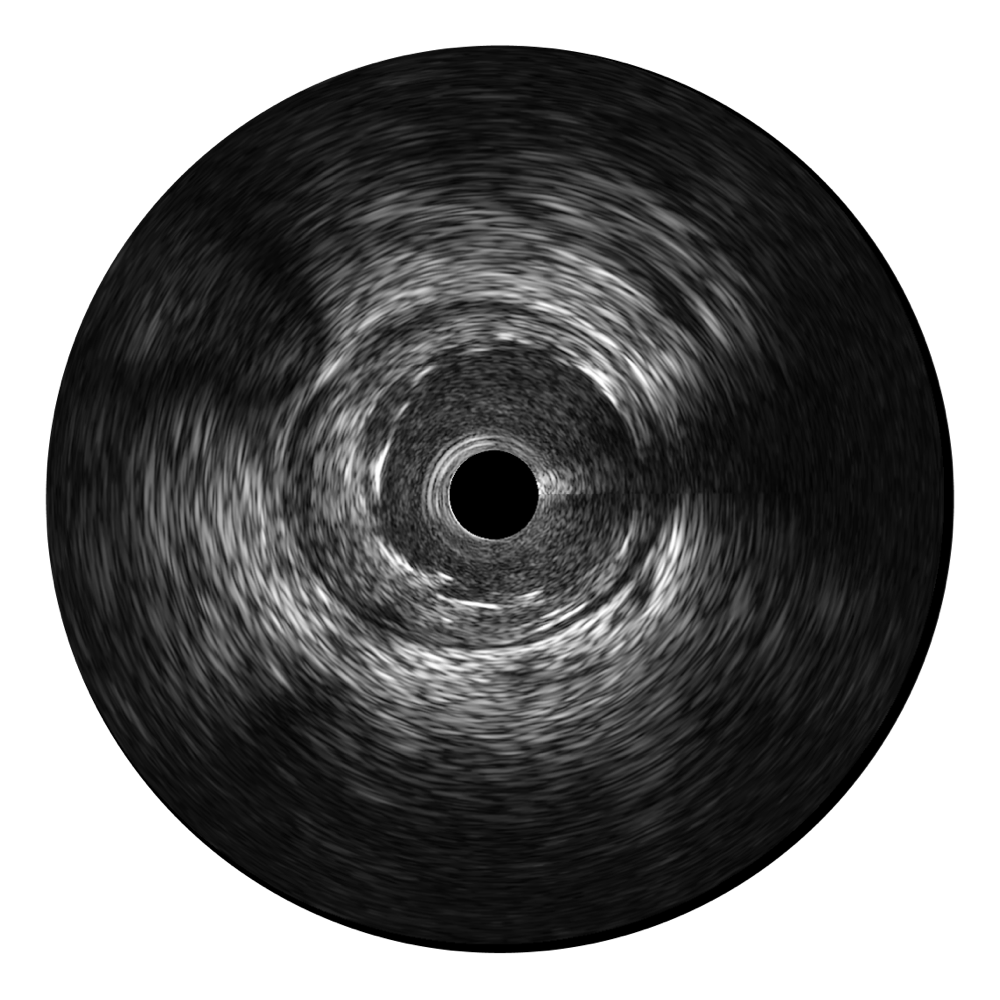

传统IVUS图像

对比传统IVUS导管成像,1xBET宽频IVUS图像的近场支架梁显影更细腻,远场中膜外血管仍清晰可辨,兼顾远中近,兼顾分辨力与穿透深度